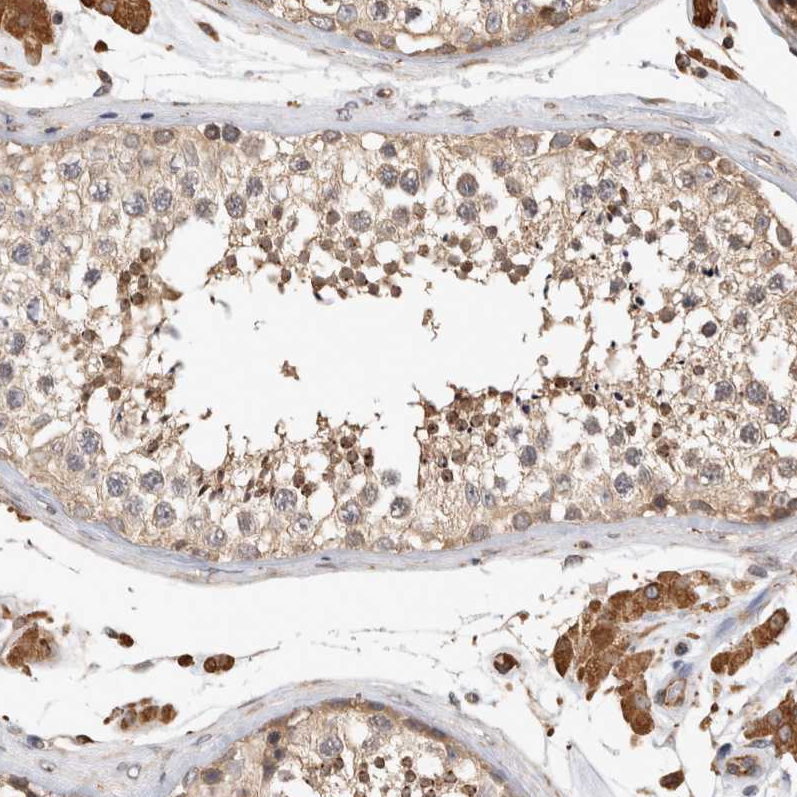

Immunohistochemical staining of human placenta shows moderate cytoplasmic positivity in trophoblastic cells.